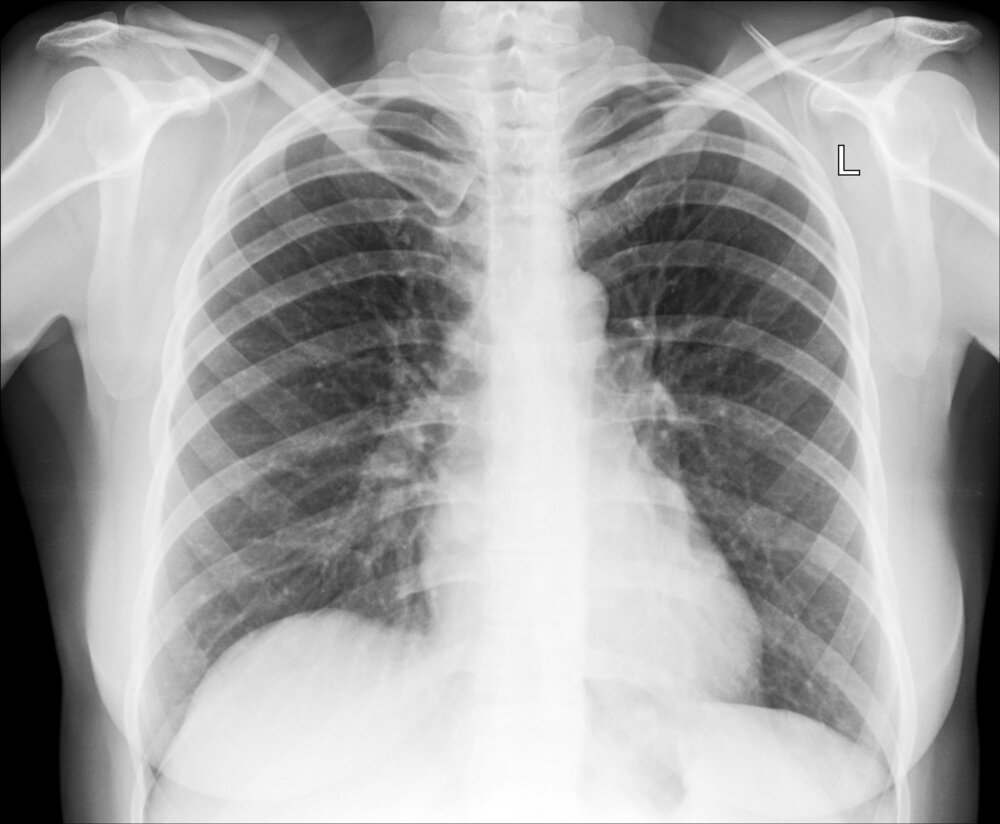

You may not know this, but x-rays can also be used to help diagnose problems in the lungs and the digestive system. Chest x-rays will have been extremely helpful recently in diagnosing the location and severity of pneumonia in COVID-19 patients.